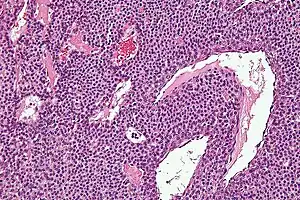

| Micrograph of a glomus tumor. H&E stain. | |

Histologically, glomus tumors are made up of an afferent arteriole, anastomotic vessel, and collecting venule. Glomus tumors are modified smooth muscle cells that control the thermoregulatory function of dermal glomus bodies. As stated above, these lesions should not be confused with paragangliomas, which were formerly also called glomus tumors in now-antiquated clinical usage. Glomus tumors do not arise from glomus cells, but paragangliomas do.